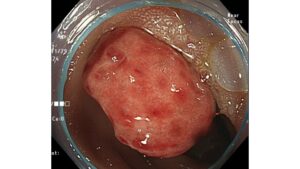

1ヶ月前から便秘と下痢を繰り返し出現した進行大腸癌の一例

2026-03-08